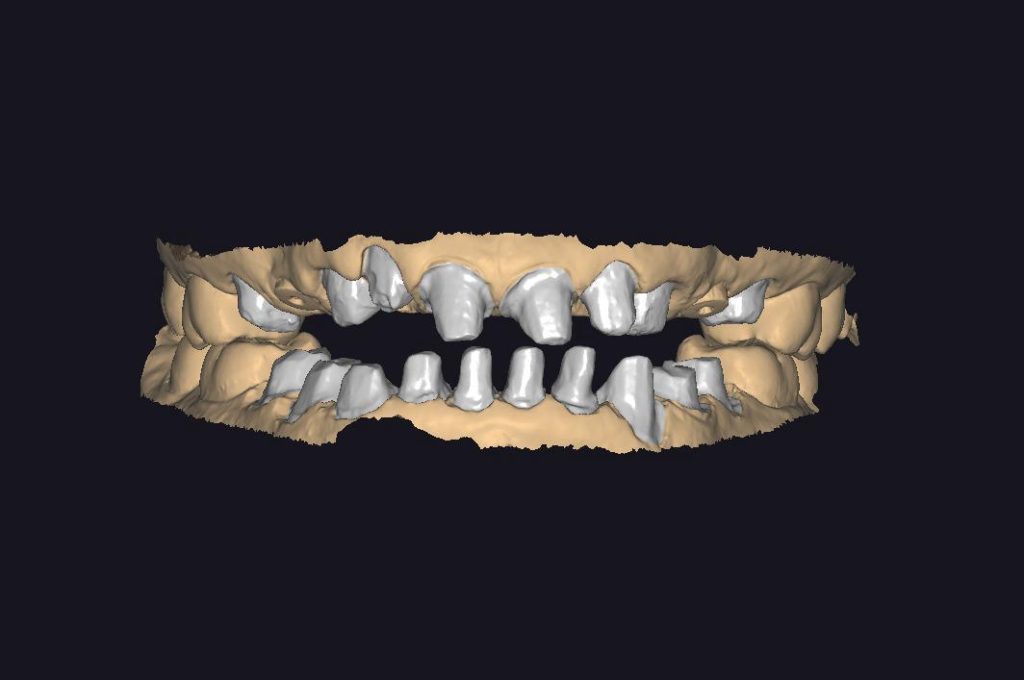

MONOLITIK ZiRKONYUM INLEY ONLEY

MULTILAYER ZiRKONYUM INLEY ONLEY

ZIRKONYUM INLEY ONLEY & LAMINATE